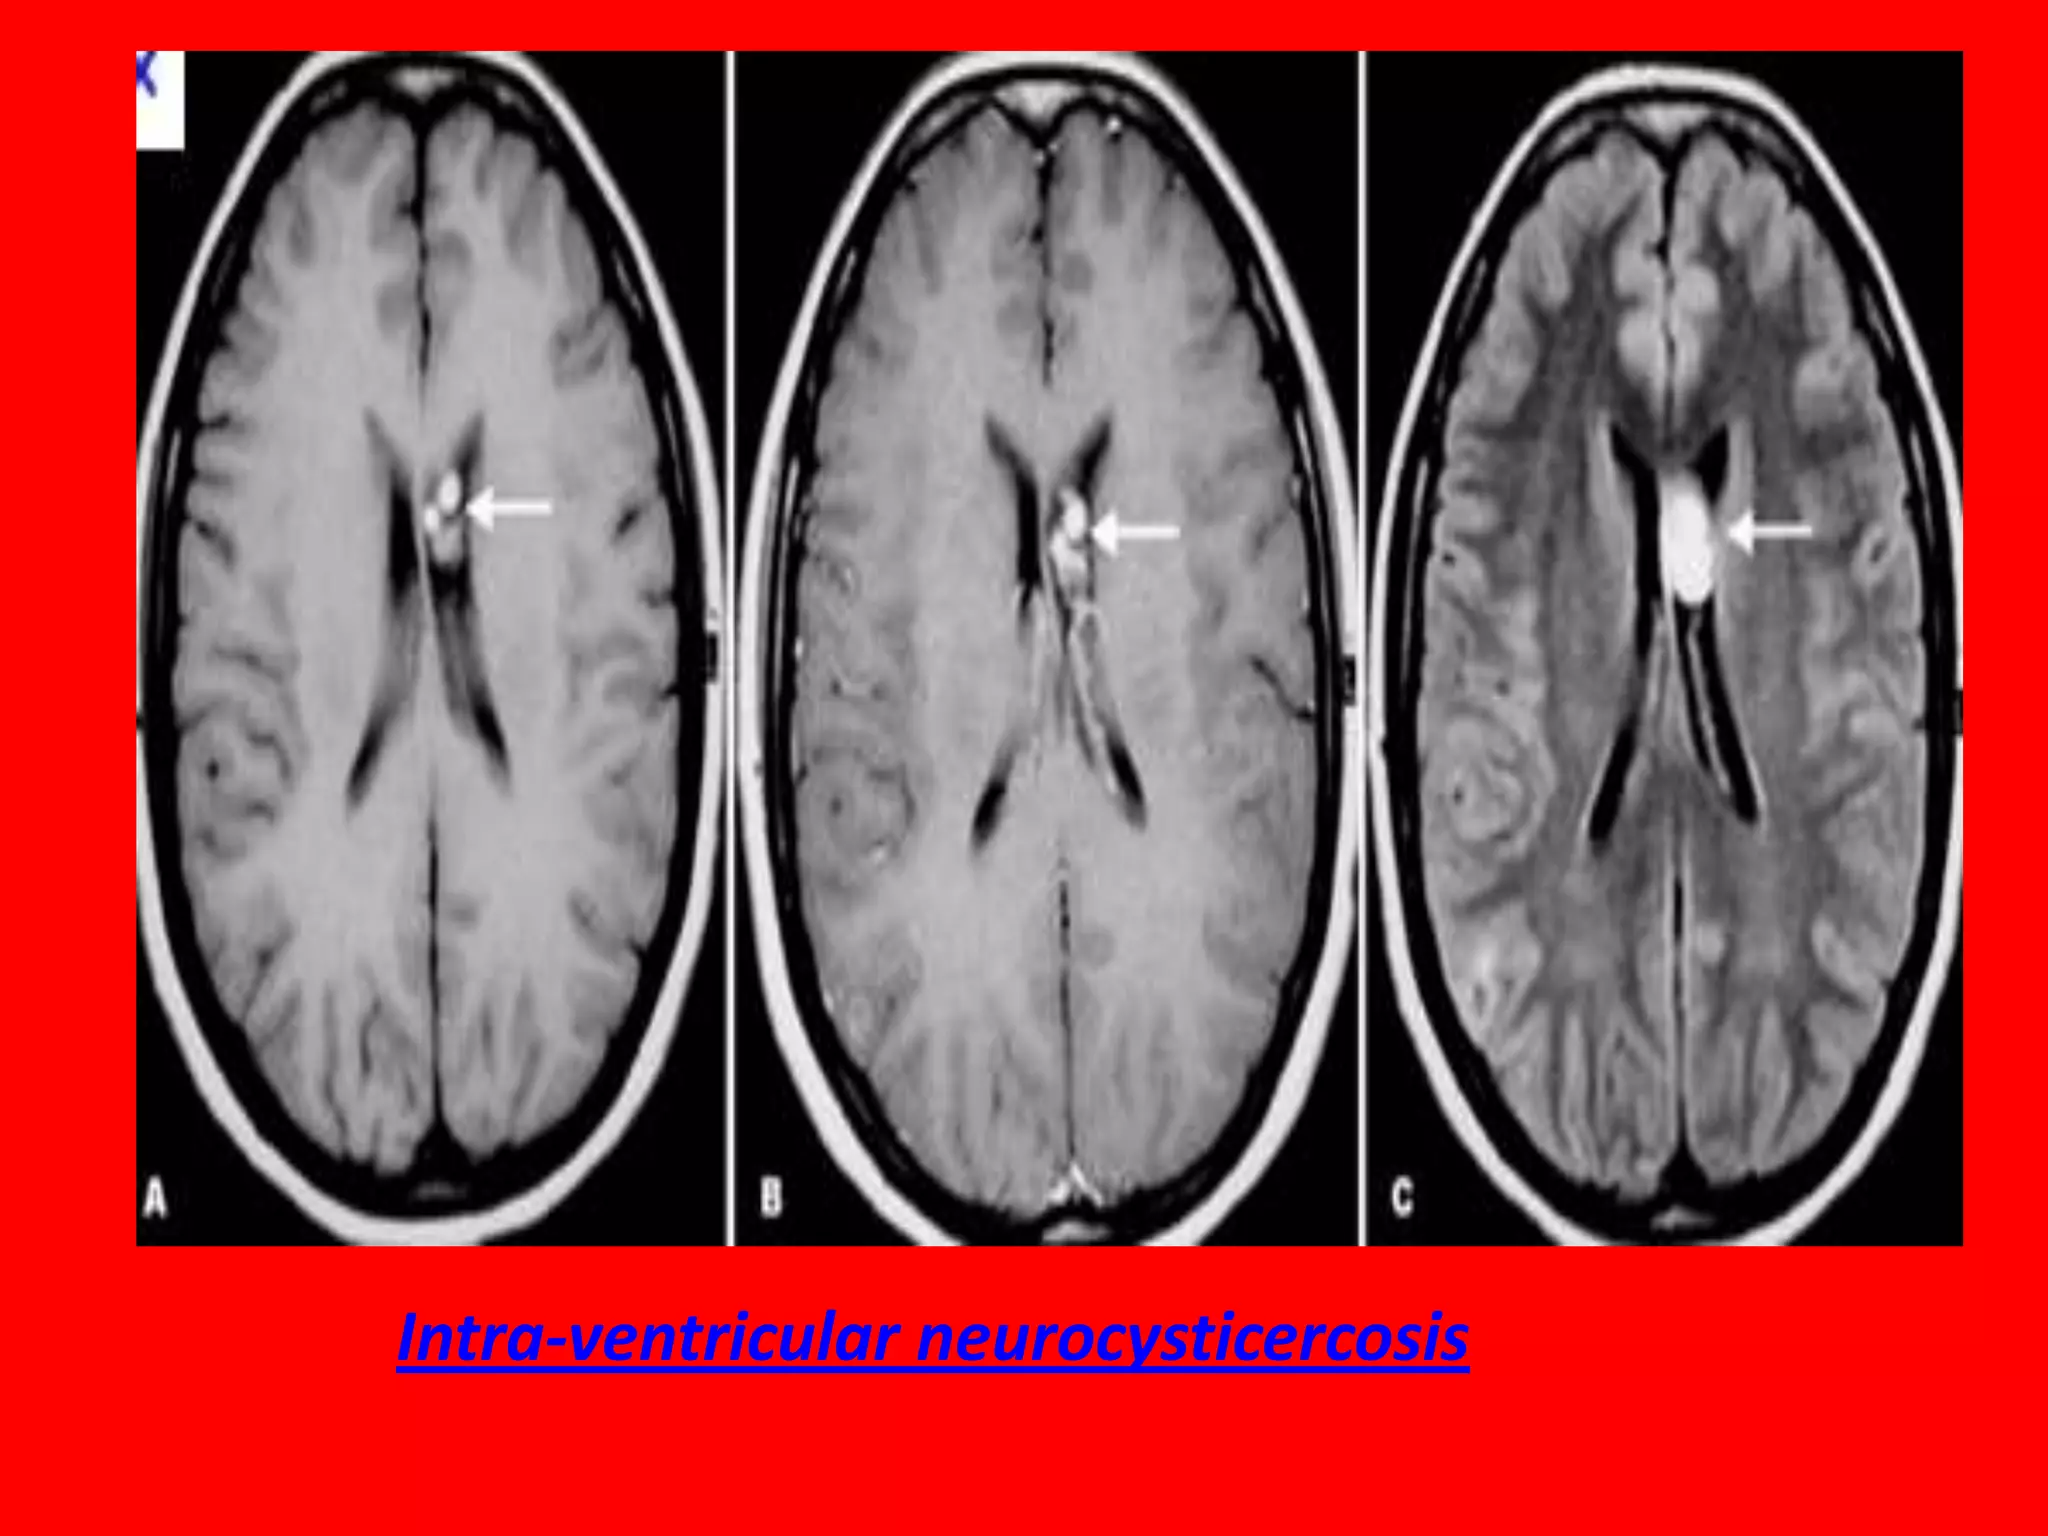

Cysticercosis is currently considered the most

common parasitic disease of the CNS. In about 10%

of neurocysticercosis cases, the cysts are found

within the cerebral ventricles or in cisterns. The

lesions are usually clinically silent until obstruction

occurs, secondary to either the location of the cystic

lesion or associated ependymitis caused by adjacent

granulomatous response. The most common

symptoms are related to hydrocephalus. The onset

of symptoms, including

headache, vomiting, seizures, can be rather sudden

and can result in death. A degenerating cyst can

cause symptoms of meningitis.

Intra-ventricular neurocysticercosis